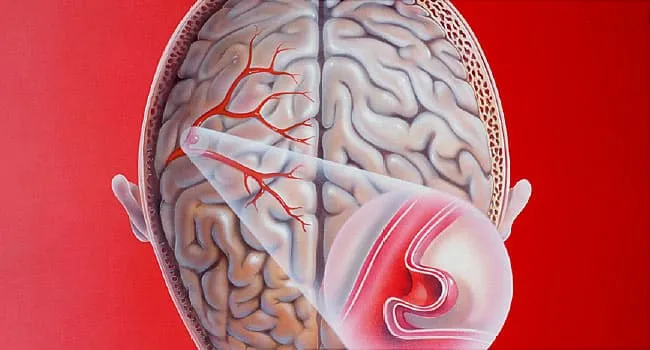

Снимки и иллюстрации микроаневризм сосудов головного мозга